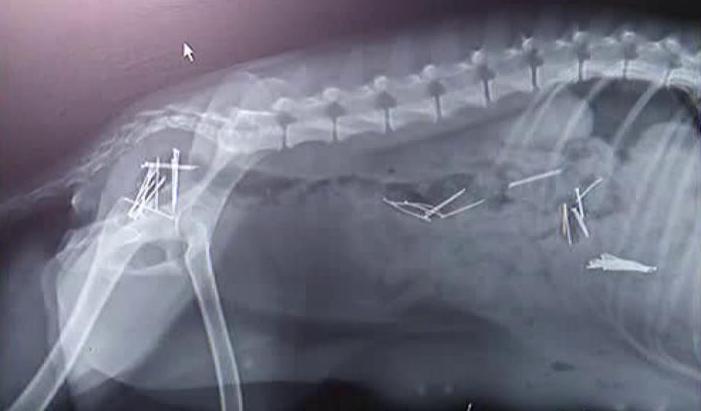

Un act de cruzime cum nici măcar medicilor veterinari nu le-a mai fost dat să vadă vreodată vine din judeţul Arad! O femeie e acuzată că a încercat să-şi omoare câinele punându-i în mâncare 45 de ace cu gămălie! ##VIDEO28213##

Desi proprietara neaga, vecinii o contrazic. Catelusa cu stomacul plin cu ace de gamalie ar fi a ei, iar tot planul diabolic l-ar fi pus la cale ca sa se razbune ca a ramas gestanta. In loc sa o fi sterilizat, femeia ar fi infometat-o, ca sa fie sigura ca bietul animal va inghiti mancarea cu ace.

"A vazut ca este gestanta si a dus-o la clinica, pentru sterilizare si dupa sterilizare au si deparazitat-o si catelusa a vomitat ace de gamalie”, spune medicul veterinar.